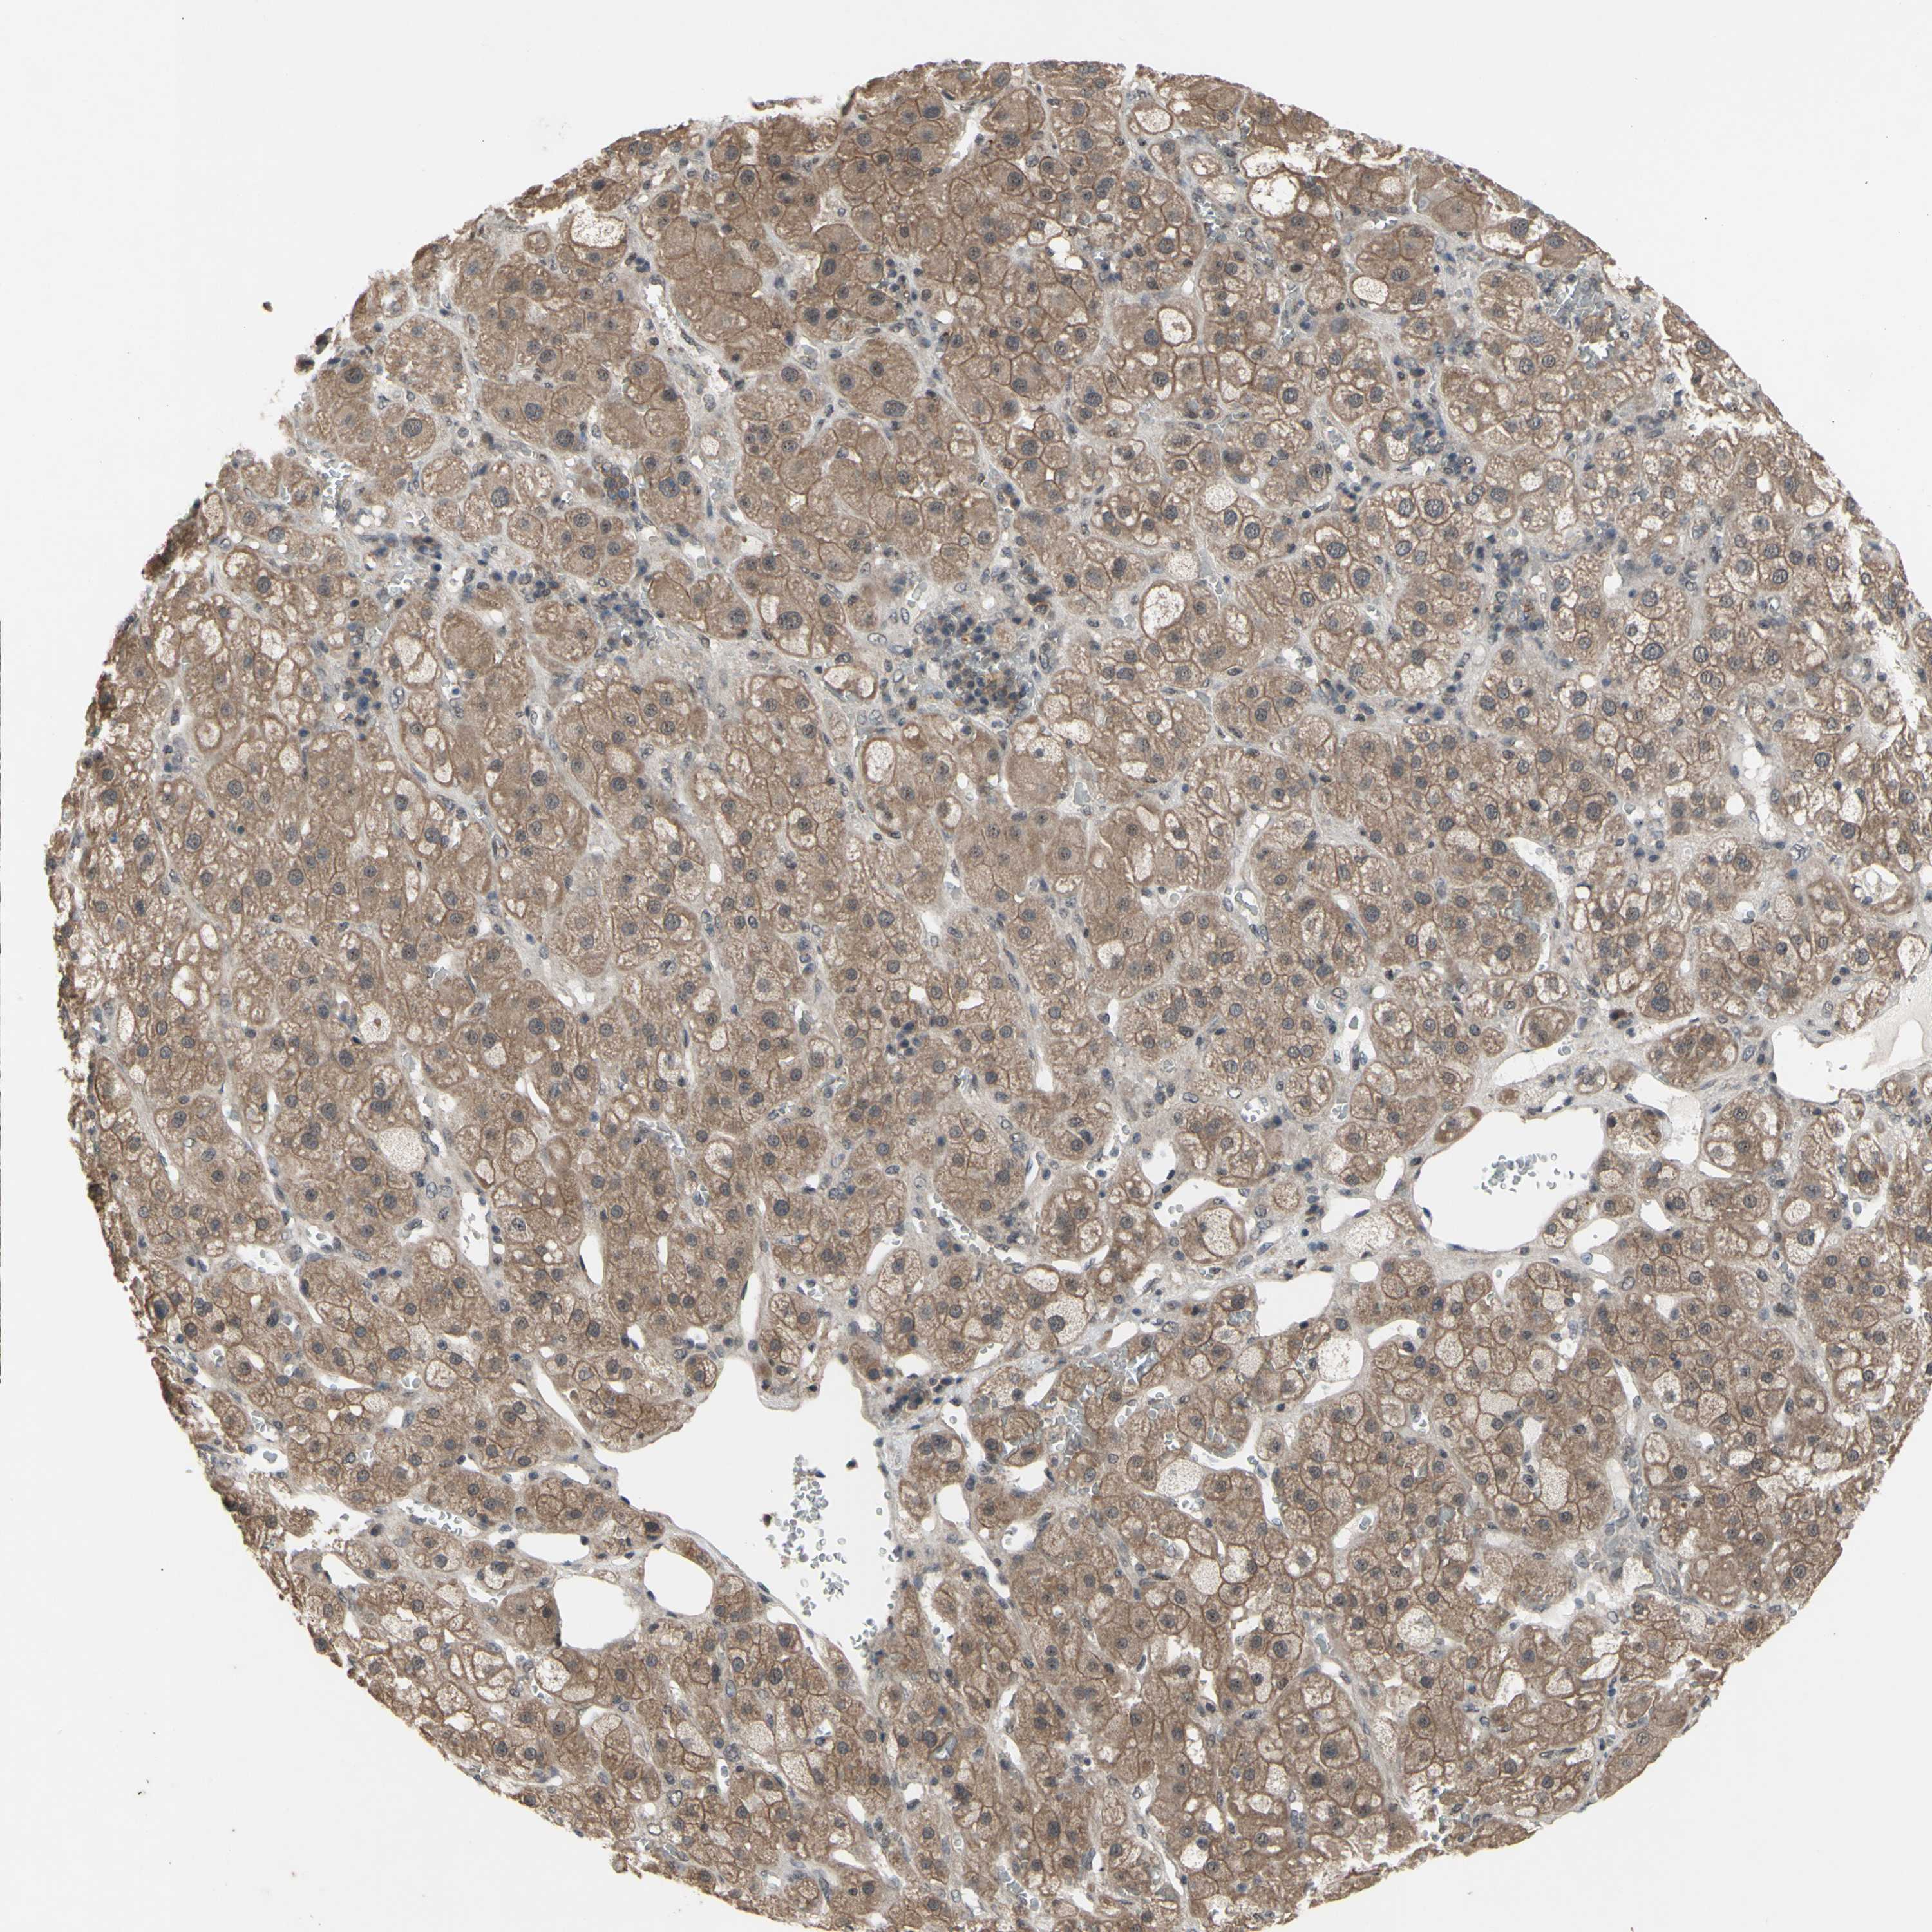

TISSUE PRIMARY DATA ADRENAL GLAND Show tissue menu

ADRENAL GLAND - Antibody stainingi

Antibody staining in the annotated cell types in the current human tissue is reported as not detected, low, medium, or high, based on conventional immunohistochemistry profiling in selected tissues. This score is based on the combination of the staining intensity and fraction of stained cells.

Each image is clickable and will lead to virtual microscopy that enables deeper exploration of all samples and also displays staining intensity scores, fraction scores and subcellular localization as well as patient and tissue information for each sample.

Antibody HPA036945Antibody HPA036946Antibody CAB009468

Glandular cells HighHighMedium